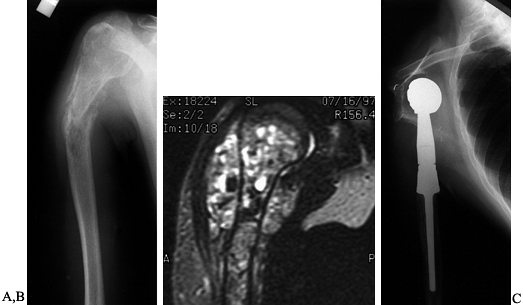

![]() |

Figure 126.25.

Osteosarcoma of the proximal humerus: staging studies and intraoperative management by resection and modular prosthetic replacement. A: Plain radiographs showing a typical sclerosing osteosarcoma (arrows) of the proximal humerus. B: Bone scan demonstrating extent of the tumor. Note: There are no other bony sites of involvement. C: Angiogram after chemotherapy showing the axillary artery and the circumflex vessels without any evidence of tumor blush. The absence of tumor vascularity is an excellent indication of response of the tumor, with marked tumor necrosis. D: Intraoperative photograph showing the Modular Replacement System (MRS, Howmedica, Rutherford, NJ). E: The postoperative radiograph following an extra-articular resection of the proximal humerus and the glenohumeral joint (type V resection). |